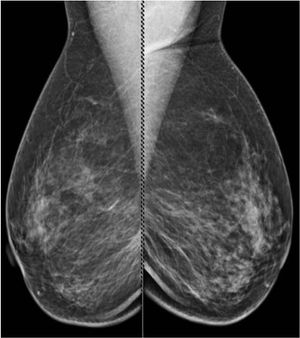

49-year-old patient presented for bilateral screening mammogram as well as bilateral screening ultrasound due to dense breast tissue.